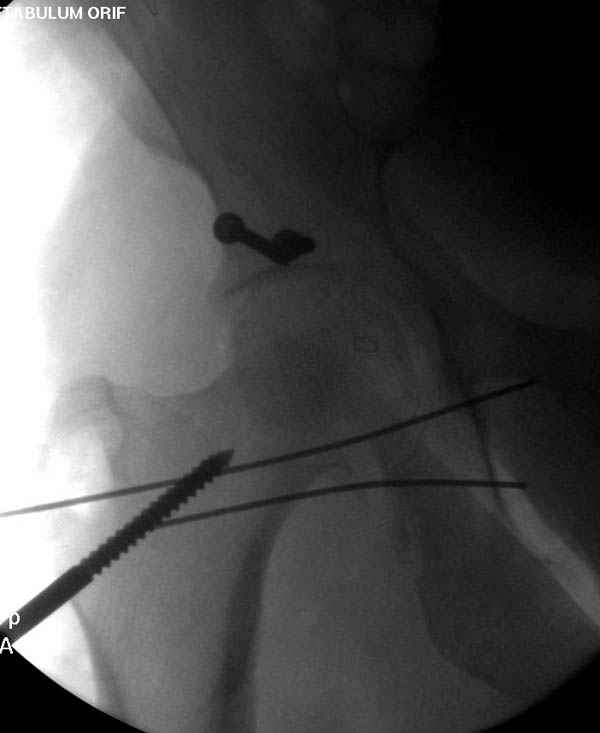

На седьмой день зафиксирован перелом ацетабулума через задний доступ. Перед операцией для профилактики DVT, IVC фильтер, также получает Lovenox.

Латеральное положение облегчает проведение тракции через вертел, за 5 мм стержень за вертел (грузом через тракционное приспособление), на обычном рентгенопрозрачном операционном столе, а для положения на животе, наверное, Judet Table более приемлем, потому что там имеется латеральное тракционное устроиство.

Там множество обычных 2.7 мм шурупов, потом идет фиксация основными пластинами.

Снимки здесь....